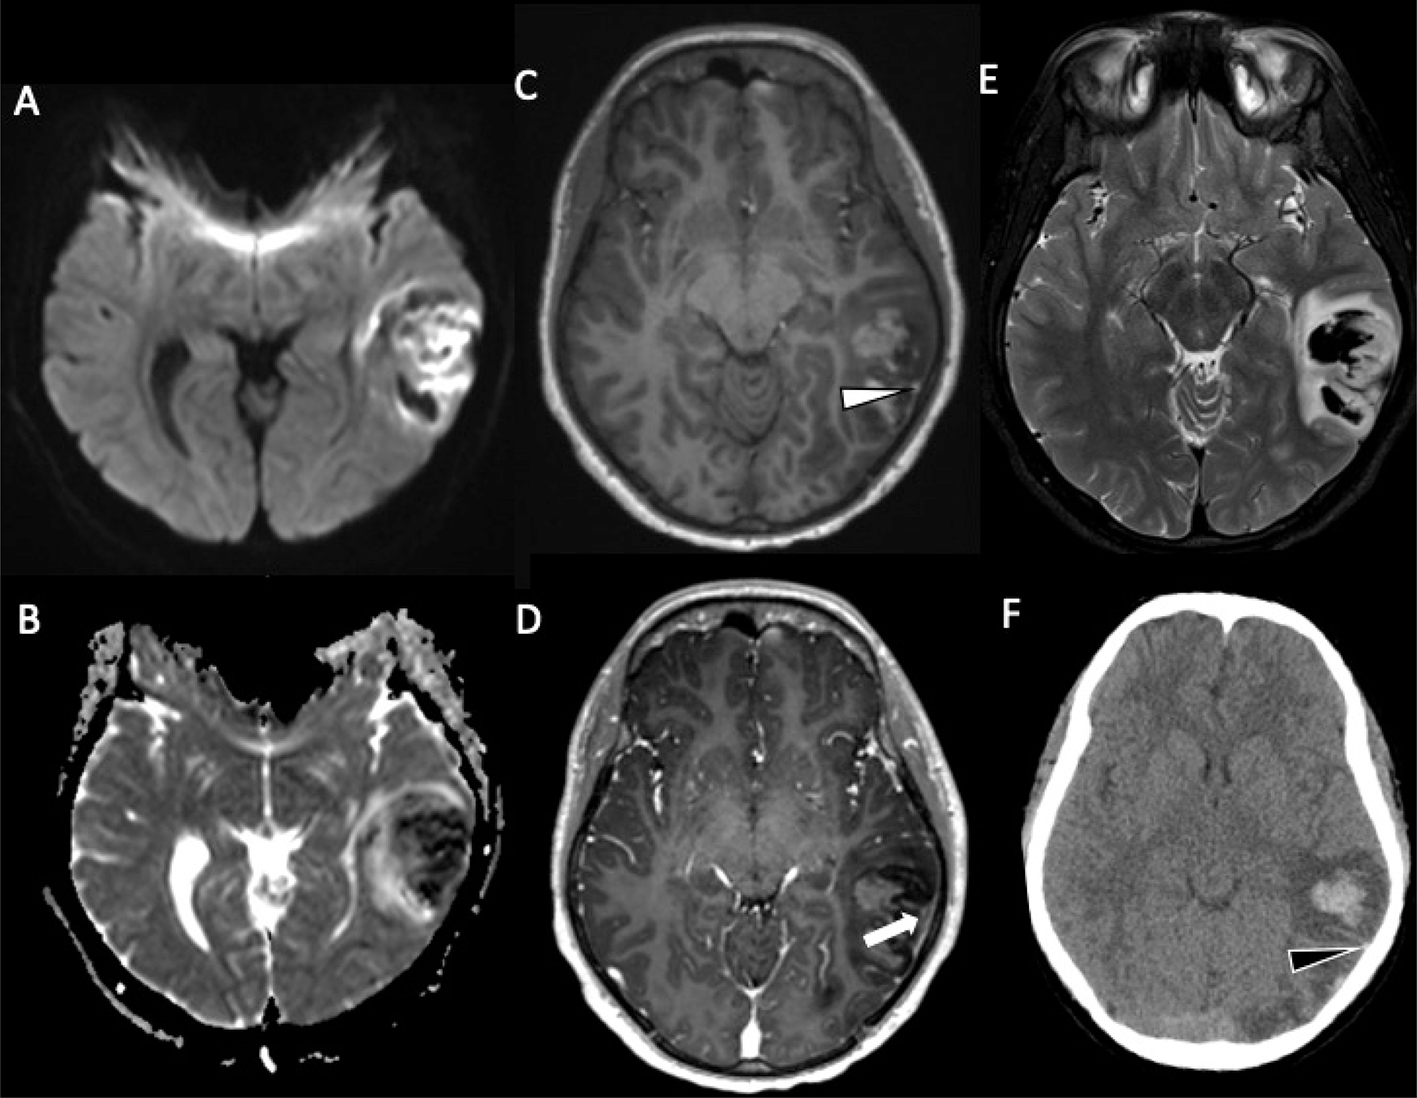

Venous sinus thrombosis and venous infarct

Venous thrombosis is a common cause of spontaneous cerebral hemorrhage, both intraparenchymal and, rarely, epidural, with nearly 70% of pediatric venous infarcts becoming hemorrhagic (Figure 8) (104, 105). Parasagittal injuries are seen with superior sagittal sinus thrombosis, temporal lobe hematomas with transverse sinus thrombosis, and thalamic hemorrhage with vein of Galen/straight sinus thrombosis.

Fig 8

Figure 8. An 18-year-old male who presented with intractable headache found to have left vein of Labbe thrombosis and hemorrhagic venous infarct. DWI (A) and associated ADC (B) demonstrates associated vasogenic and cytotoxic edema. Noncontract T1-weighted image (C) shows high signal within the left vein of Labbe (white arrowhead) with associated filling defect on contrast enhanced study (white arrow) (D). No underlying vascular malformation or mass was identified. T2-weighted MRI (E) demonstrates a left posterior temporal hematoma with associated edema. Noncontrast axial CT image (F) demonstrates parenchymal hemorrhage with hyperdensity within the vein of Labbe (black arrow).